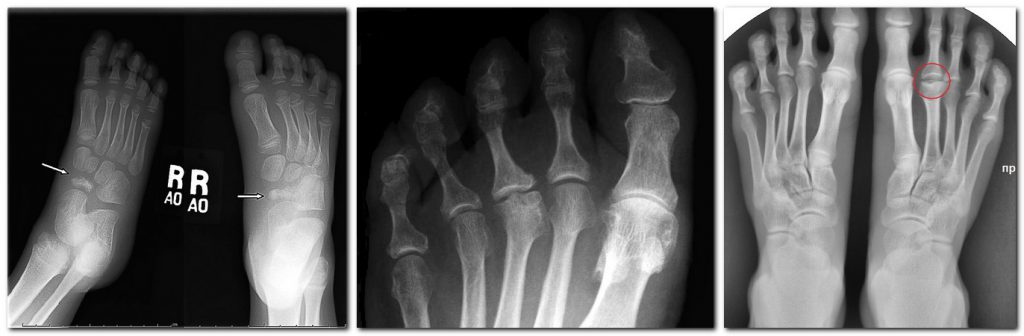

Келлера 4

Келлера 4 115 фото